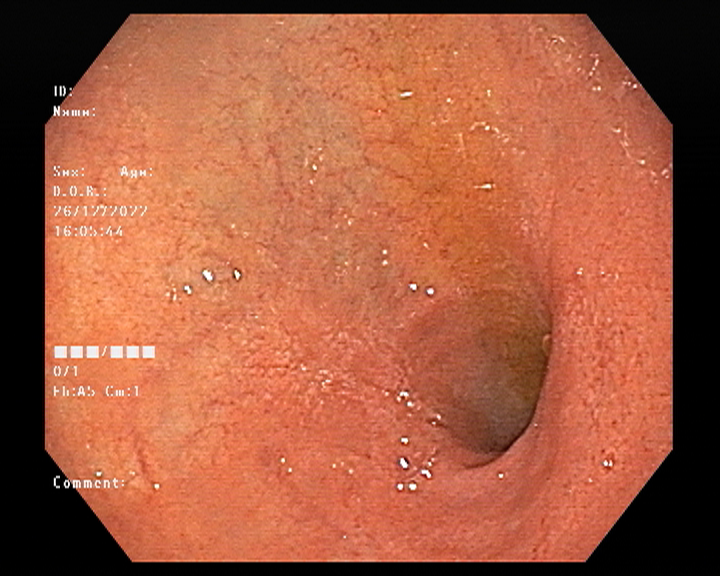

Endoscopy and colonoscopy are safe and accurate procedures used to directly examine the digestive tract and detect the root cause of chronic acidity, GERD, abdominal pain, bleeding, and bowel irregularities. These minimally invasive tests help identify ulcers, inflammation, infections, polyps, strictures, and early cancerous changes.

At Sapphire Gastroenterology Center, modern endoscopic equipment ensures precise diagnosis and, when required, therapeutic intervention during the same procedure. Based on findings, targeted treatment plans are created, including medication, diet guidance, and preventive strategies. Early diagnosis through endoscopy and colonoscopy plays a crucial role in preventing serious complications and improving long-term digestive health.